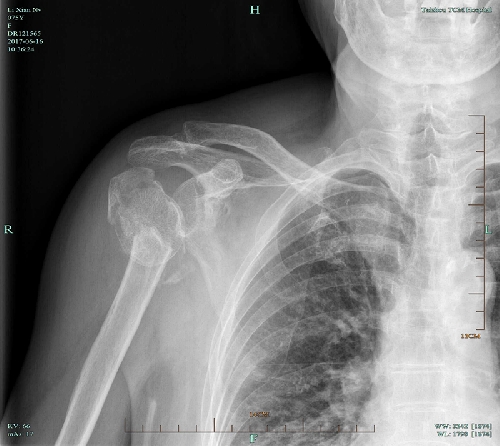

近日,我院骨三科獨(dú)立完成了首例 “人工肱骨頭置換術(shù)”?;颊呃頧X,女,75歲,因摔傷致右肩腫痛、活動(dòng)不利4小時(shí)入院。查體判斷:右肩部無(wú)腫脹,局部壓痛,縱向叩擊痛陽(yáng)性,右肩上舉、外展受限,肢端血循、感覺(jué)良好。X片示:右肱骨近端粉碎性骨折,移位明顯。CT示:右肱骨上端骨質(zhì)斷裂,呈粉碎性,大、小結(jié)節(jié)骨折,斷端位置差,關(guān)節(jié)在位。診斷為:右肱骨近端粉碎性骨折(四部分骨折)。為了緩解患者疼痛,改善肩關(guān)節(jié)功能,提高生活自理能力,經(jīng)科室討論決定,對(duì)于高齡肱骨近端粉碎性四部分骨折,應(yīng)采用人工肱骨頭置換術(shù)。

術(shù)前X片正位 術(shù)前X片穿胸位